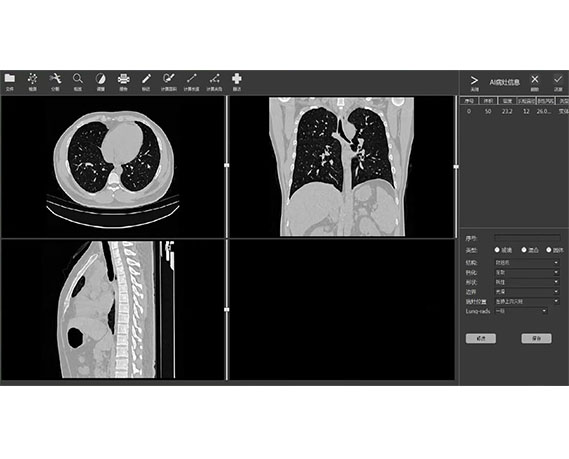

成像智能。

Eclipse 成像智能功能提供强大的处理能力和最佳质量的影像,同时减少质量错误并提高剂量效率。

凭借 AI、专有算法和先进的影像处理能力,提供出色的影像质量和无与伦比的诊断信心。

与标准影像处理相比,智能降噪功能可使客户降低辐射剂量,而不会损失影像质量。这在新生儿和儿科成像中尤其重要,在这种情况下以尽可能低的剂量成像至关重要。

提供相配视图选项,以减少所需的曝光次数,并提供更清晰的感兴趣区域视图。